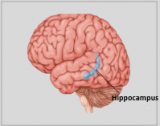

Die Neuroanatomie ist das Teilgebiet der Anatomie, das sich mit der Anatomie des Nervensystems befasst, d. h. mit der Struktur, Funktion und Organisation des Nervensystems. Das Nervensystem ist eines der komplexesten Systeme im menschlichen Körper und umfasst das Gehirn, das Rückenmark, die peripheren Nerven und die Nervenganglien. Die Neuroanatomie befasst sich damit, wie diese Strukturen miteinander verbunden sind, wie Signale zwischen den Nervenzellen übertragen werden und wie die verschiedenen Teile des Nervensystems zusammenarbeiten, um körperliche und kognitive Funktionen zu steuern. Neuroanatomen verwenden fortschrittliche bildgebende Verfahren wie Magnetresonanztomographie (MRT), Positronenemissionstomographie (PET) und Mikroskopie, um die Strukturen und Funktionen des Nervensystems sichtbar zu machen.